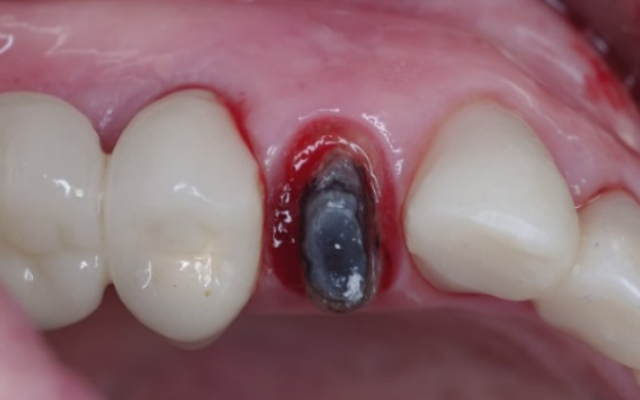

Crown lengthening surgery is a procedure that is carried out by your periodontist to expose more tooth structure (Figure 9A). Crown lengthening is normally required either for functional reasons, or for cosmetic reasons.

Functional crown lengthening is required if there is insufficient tooth structure to enable your dentist to provide a retentive and long-lasting restoration (Figures 9B & C). This may be because your tooth is broken, worn, or cracked or if there is extensive decay extending below the gum line.

Crown lengthening to expose more sound tooth structure.